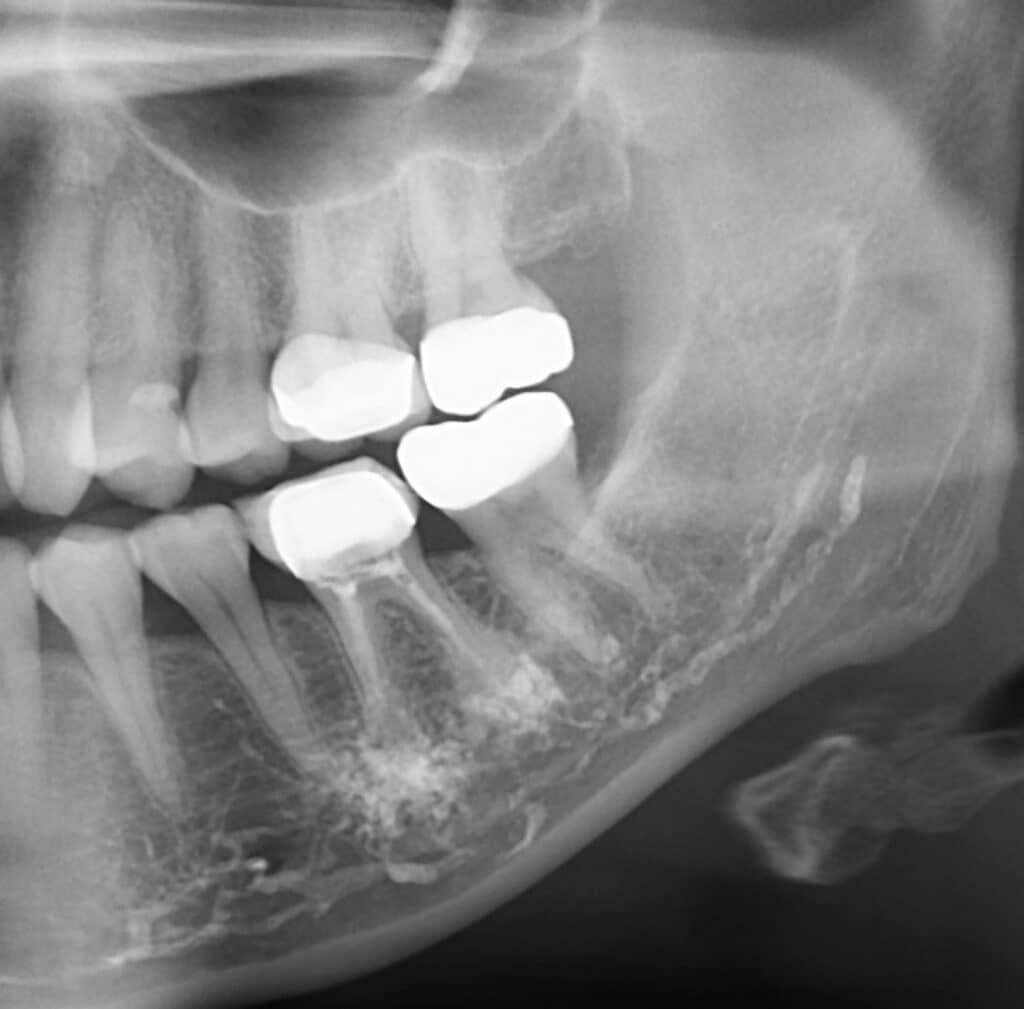

(a, b) Radiography of orthodontic extrusion with chain and after tooth What Is Tooth Extrusion Orthodontic extrusion (oe) is an orthodontic tooth movement in a coronal direction to modify the tooth position and/or induce changes on the. Orthodontic extrusion (oe) is an orthodontic tooth movement in a coronal direction to modify the tooth position and/or induce changes on the surrounding bone and. Orthodontic extrusion helps to enhance the restorability of a tooth. An injury to. What Is Tooth Extrusion.

(a, b) Radiography of orthodontic extrusion with chain and after tooth What Is Tooth Extrusion An injury to the tooth characterized by partial or total separation of the periodontal ligament resulting in loosening and. Orthodontic extrusion (oe) is an orthodontic tooth movement in a coronal direction to modify the tooth position and/or induce changes on the surrounding bone and. Orthodontic extrusion (oe) is an orthodontic tooth movement in a coronal direction to modify the tooth. What Is Tooth Extrusion.